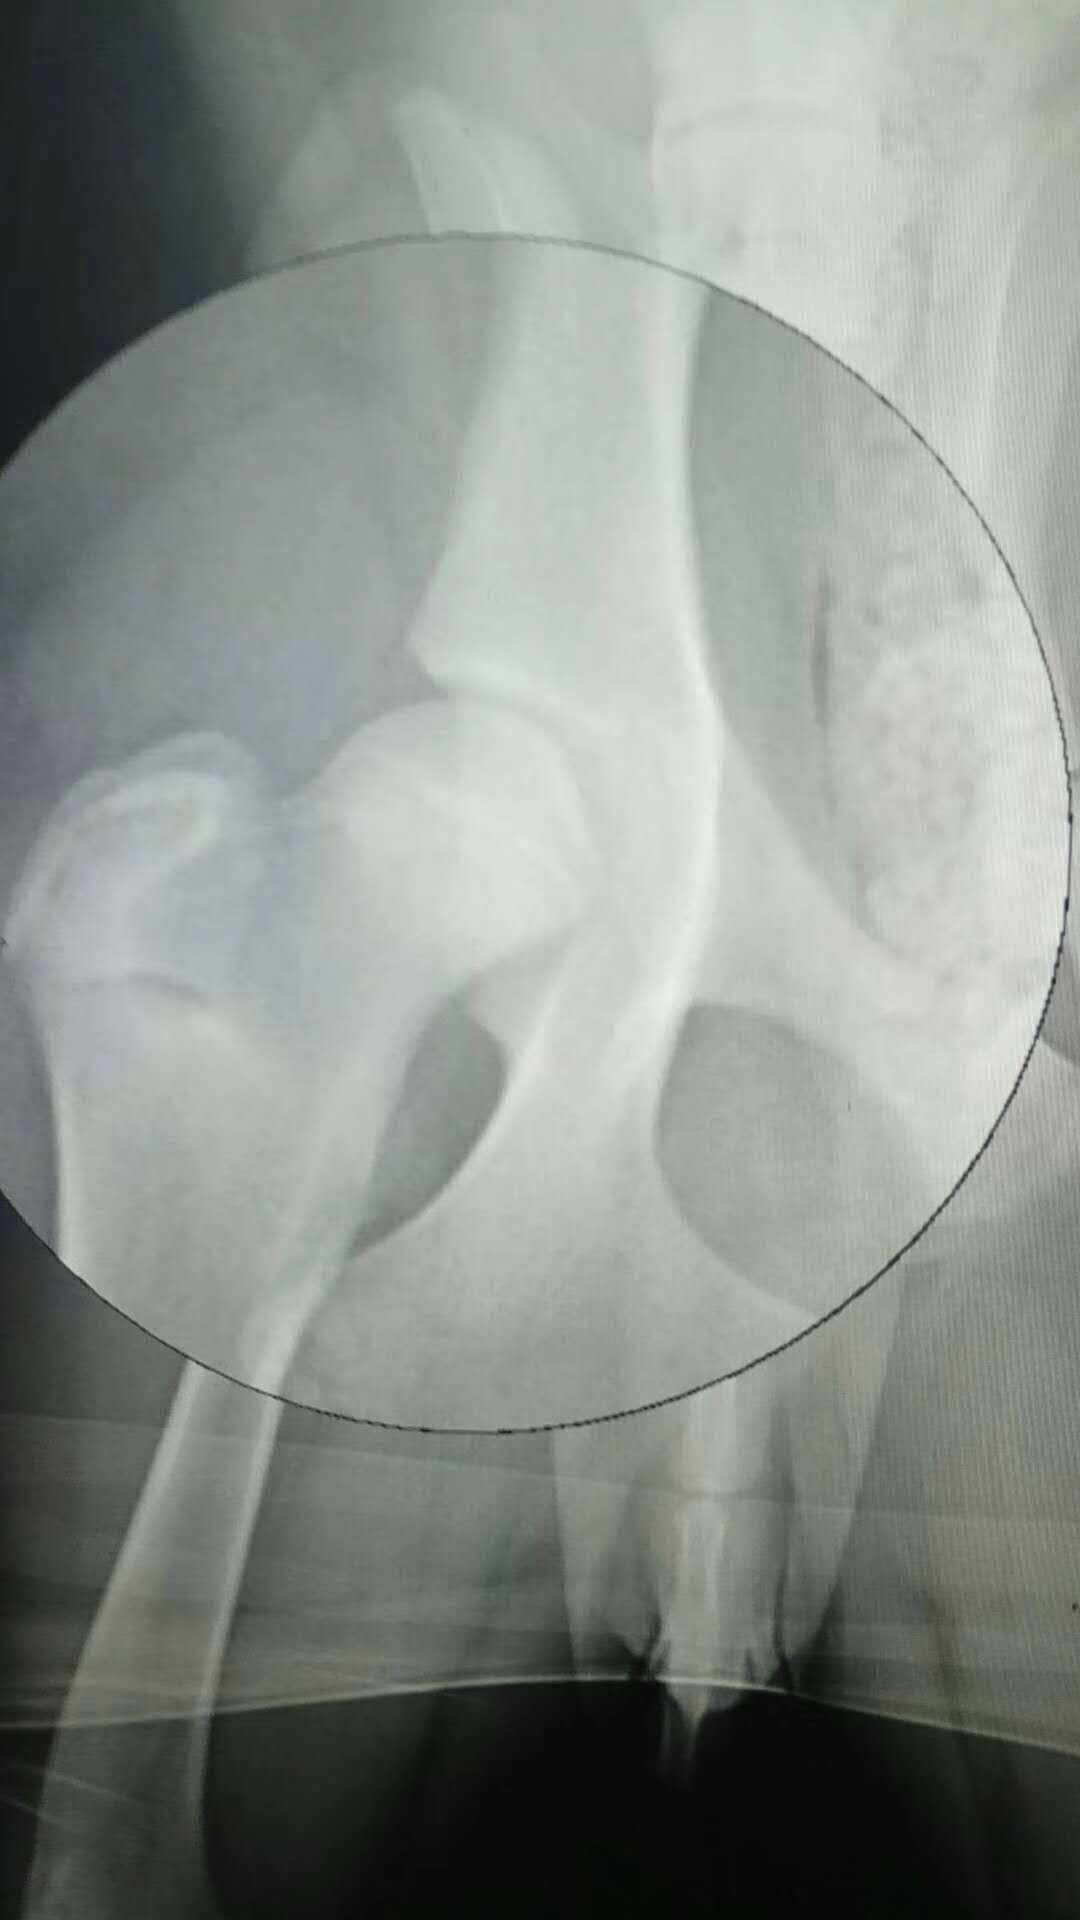

髖關(guān)節(jié)發(fā)育不良病例:金毛,SIRI,近期主人發(fā)現(xiàn)走路或跑動(dòng)時(shí),后肢姿勢異常,不敢用力,偶有疼痛,帶來檢查確診為髖關(guān)節(jié)發(fā)育不良,帶藥保守治療中。